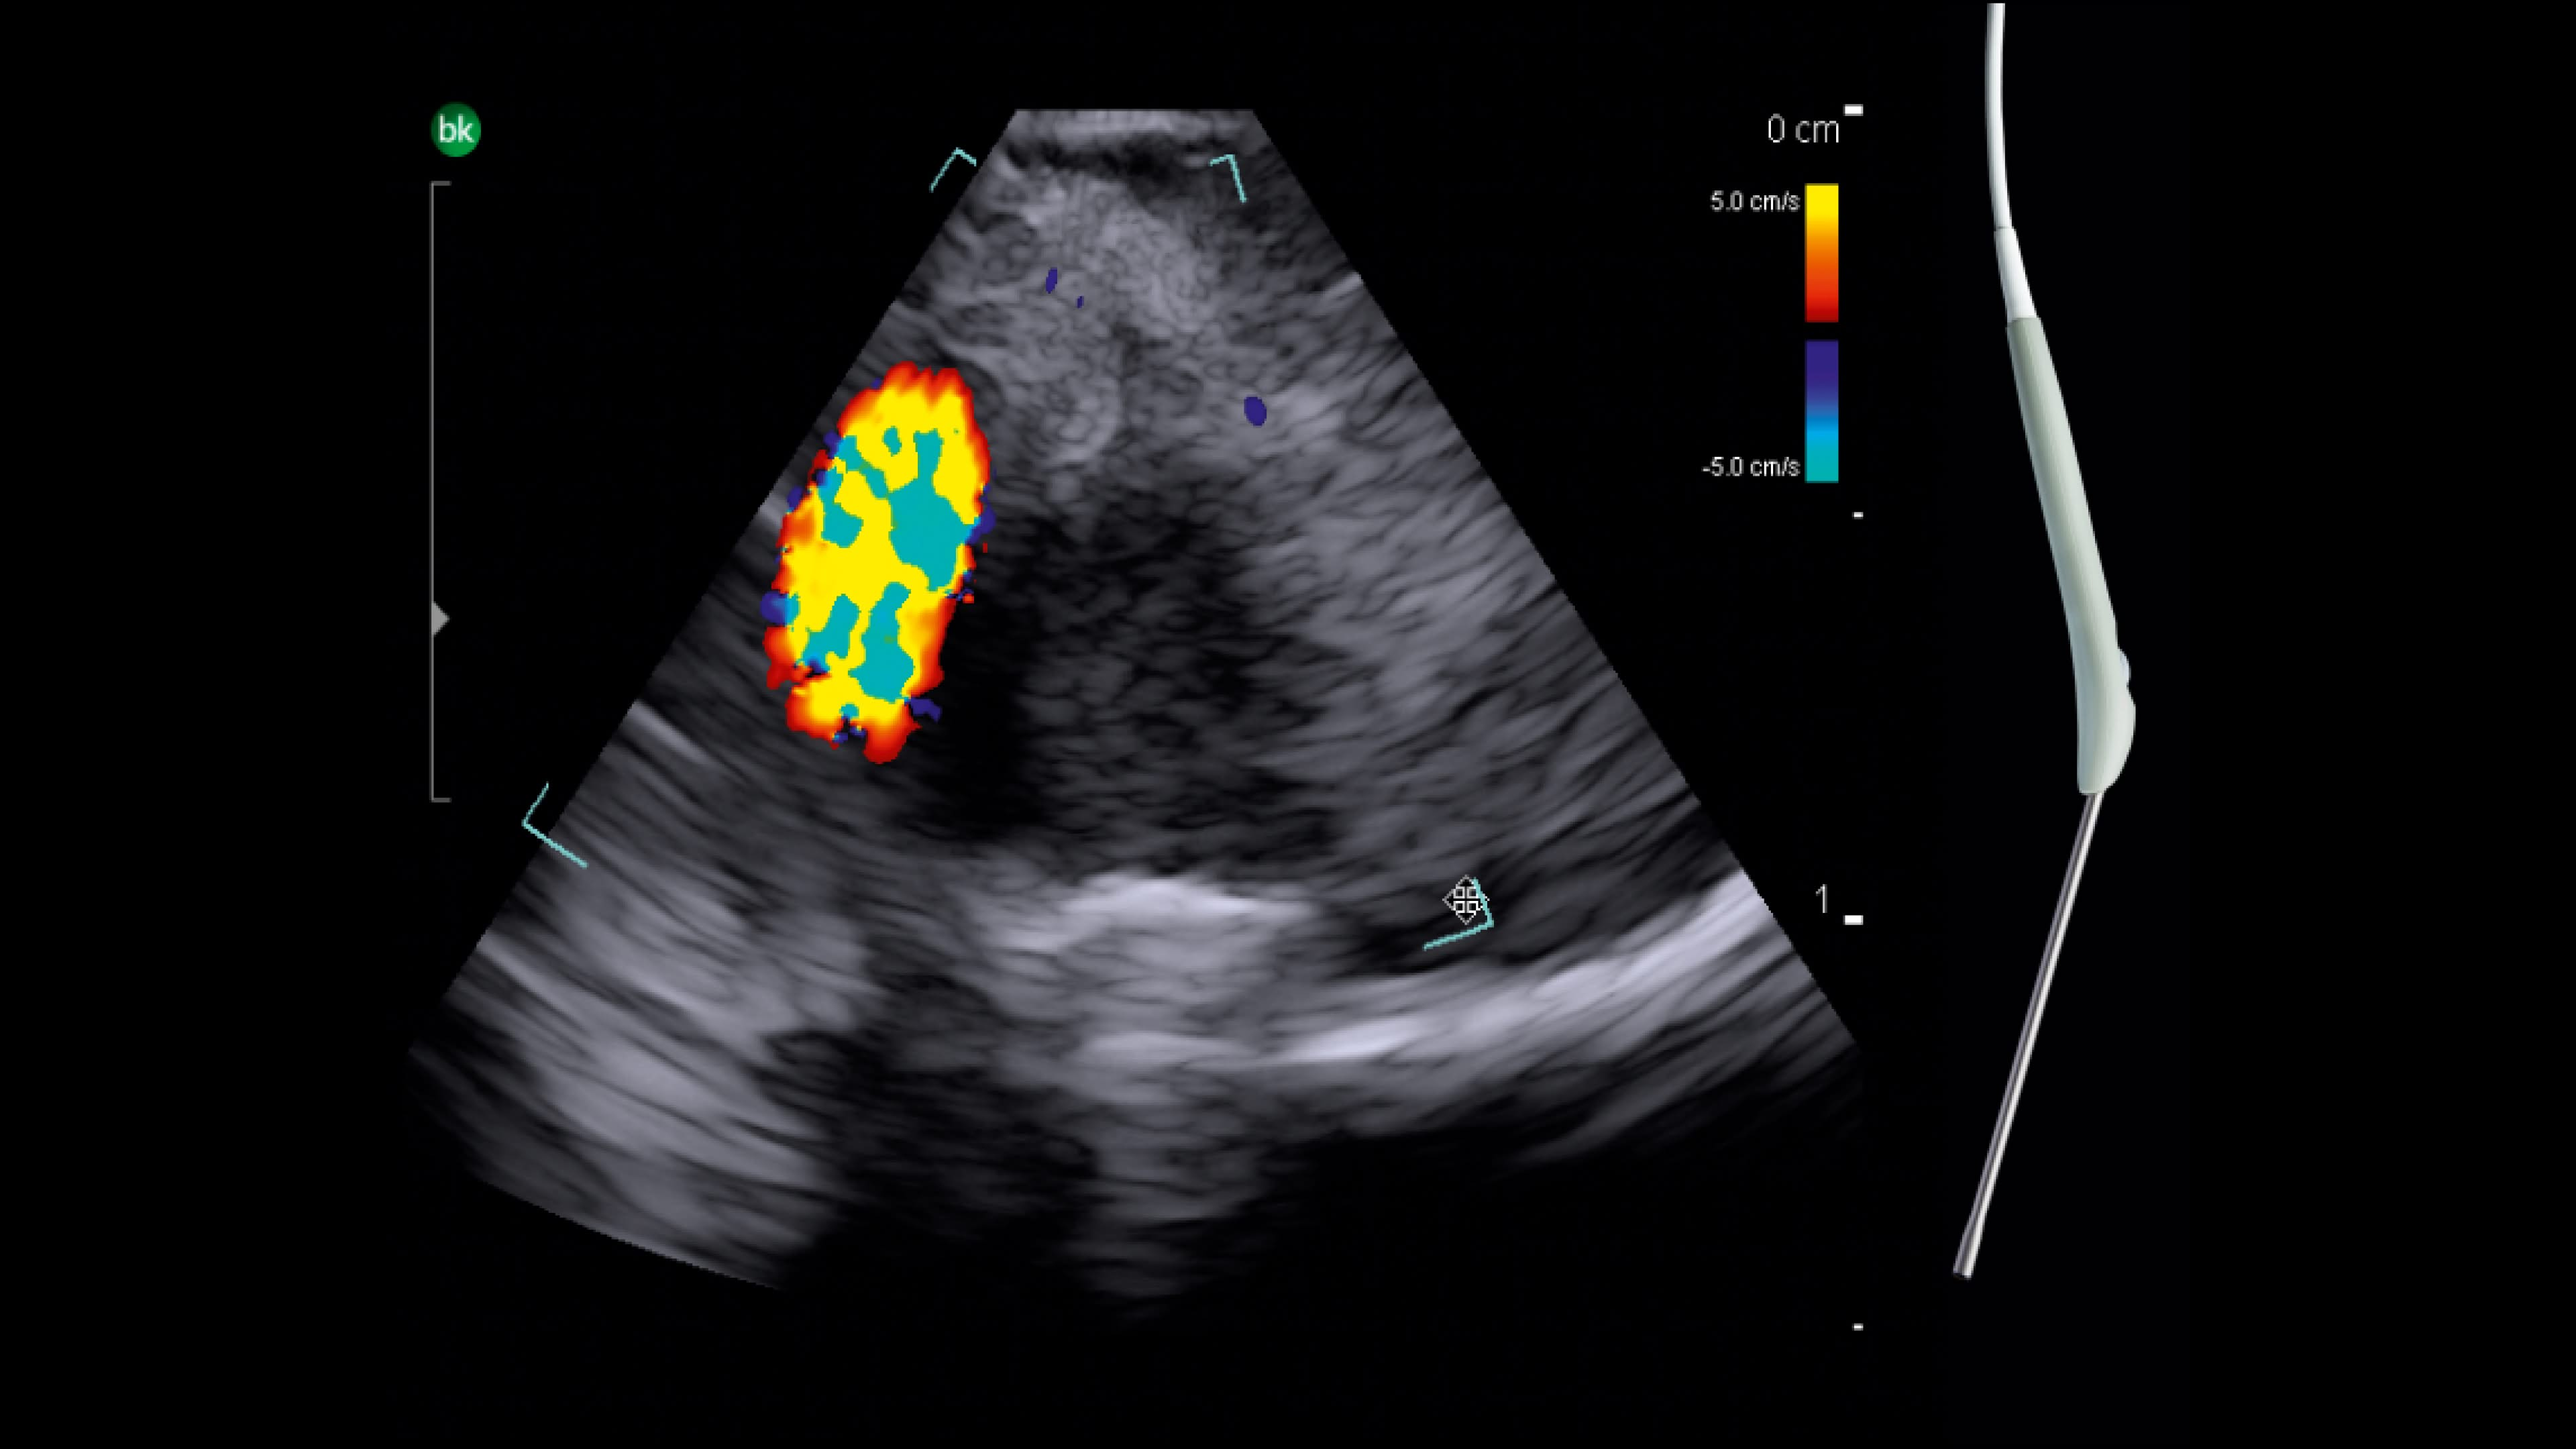

Neurovascular

Shorten operative time with intraoperative ultrasound³. Use intraoperative ultrasound during surgery to: locate AVM nidus and identify feeding arteries with color Doppler, assess for resection of AVMs⁴, identify associated hematoma⁵, and visualize preoperative embolization (e.g. Onyx®).